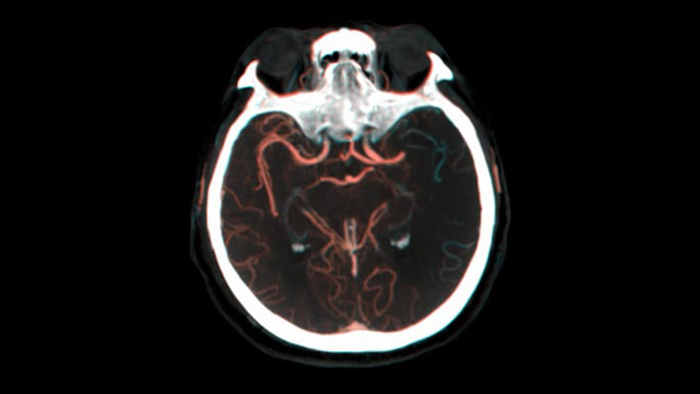

Consulte enchimento colateral

Visualização de enchimento colateral

A vista dupla para visualização de volumes de TC de feixe cónico de fase precoce e tardia lado a lado melhora a identificação da penumbra e permite a visualização do enchimento colateral.

Três CT inteligentes

Visualização semelhante a TC

O SmartCT Soft Tissue  gera uma visualização tipo TC dos tecidos moles e suporta o diagnóstico de acidentes vasculares cerebrais de três formas. Um exame sem contraste ajuda na deteção de alterações isquémicas precoces. Um exame de fase precoce ajuda a identificar a oclusão proximal. Um exame melhorado de contraste de fase tardia suporta a deteção de colaterais.